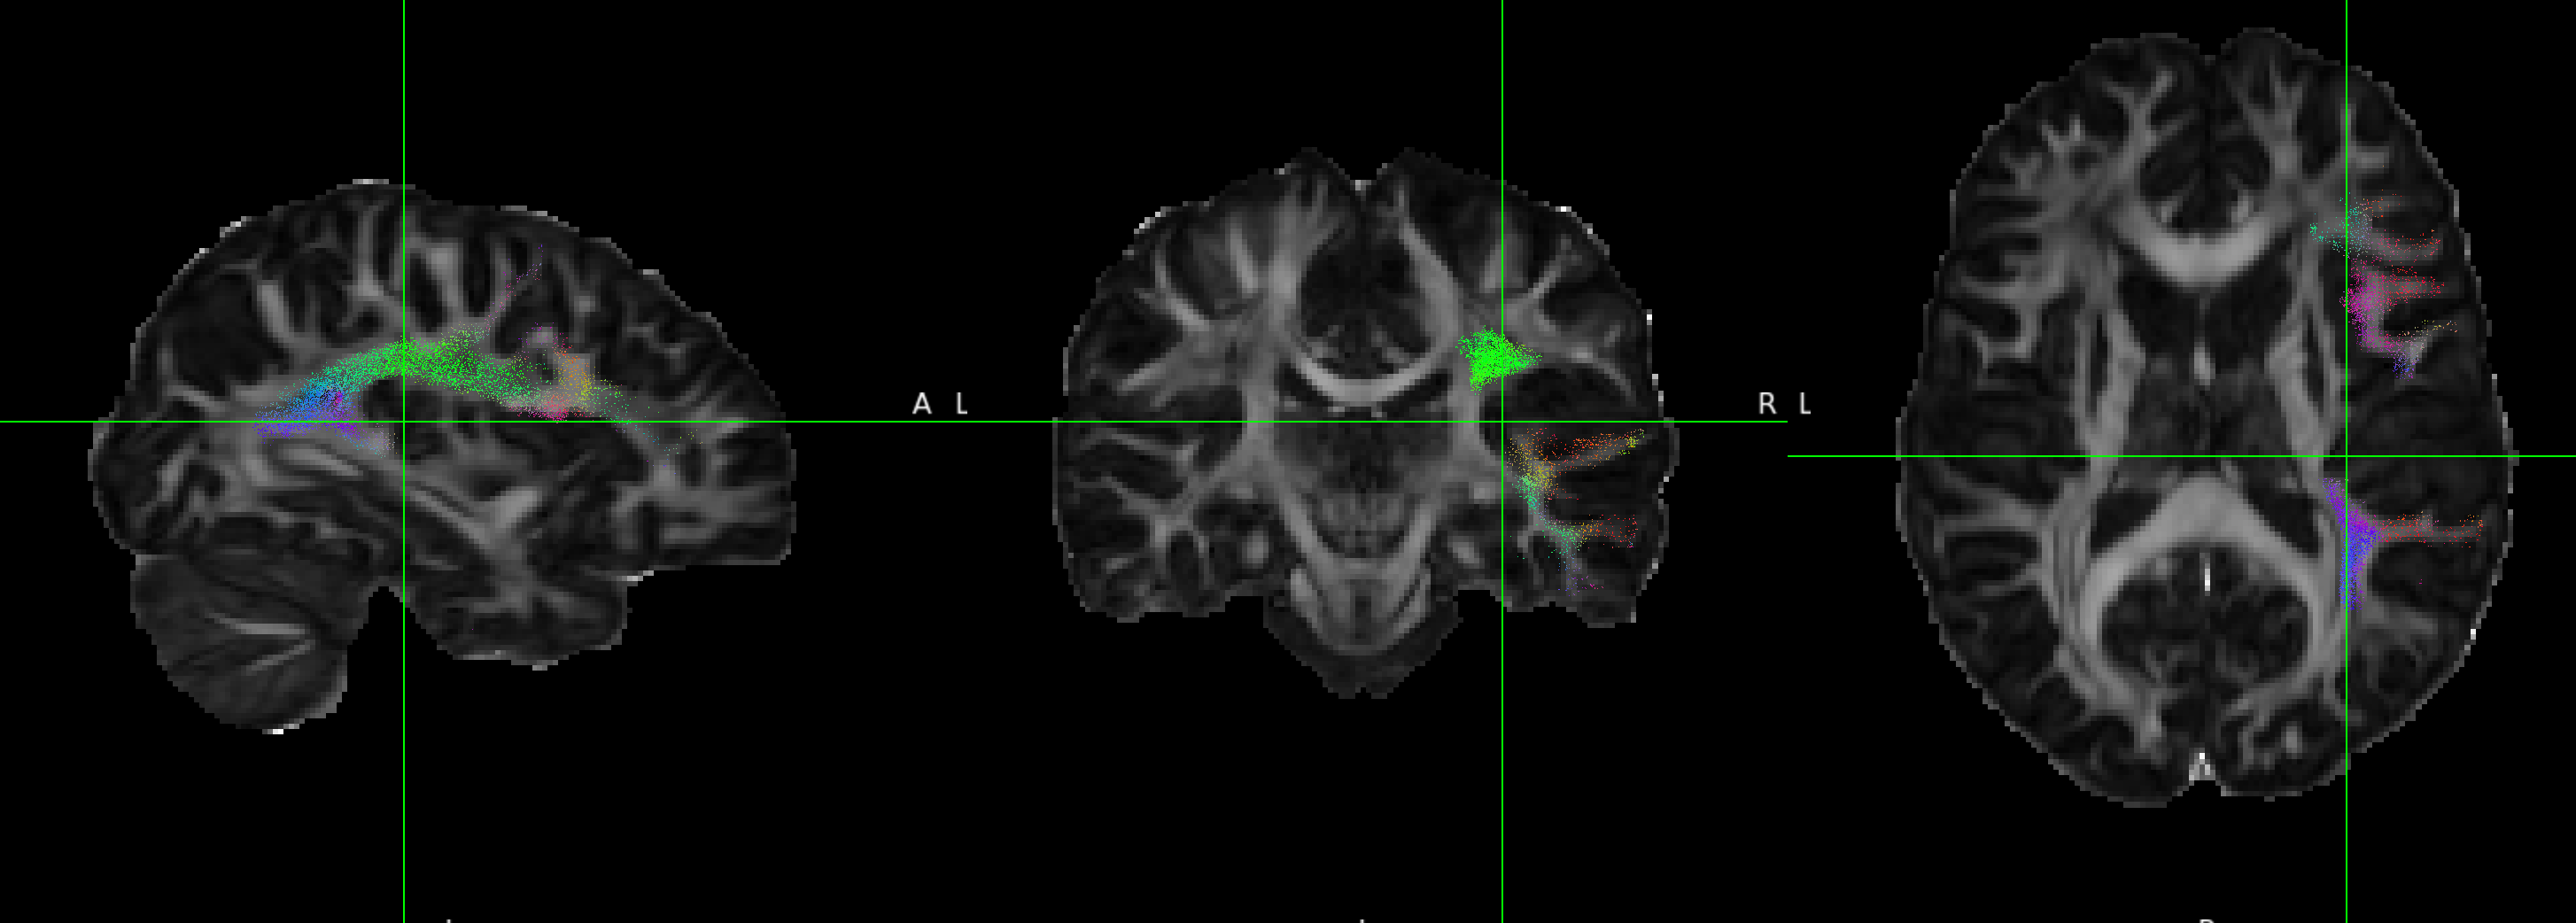

I noticed that in the master branch, compared to 2.3 that I used previously, tract files (I have tested on both --tracking_format tck and trk) are no longer in DWI space. When I load the tck/trk file in MRView/FSLeyes, the tract file is out of bounds of the DWI reference image (in this case, I used FA).

In version 2.3, as seen below with the left AF, trk and tck map onto the image (top is trk in FSLeyes, bottom is tck in MRView). However, it is worth noting that the left AF appears on the wrong hemisphere for the trk file, while the tck file is correct: